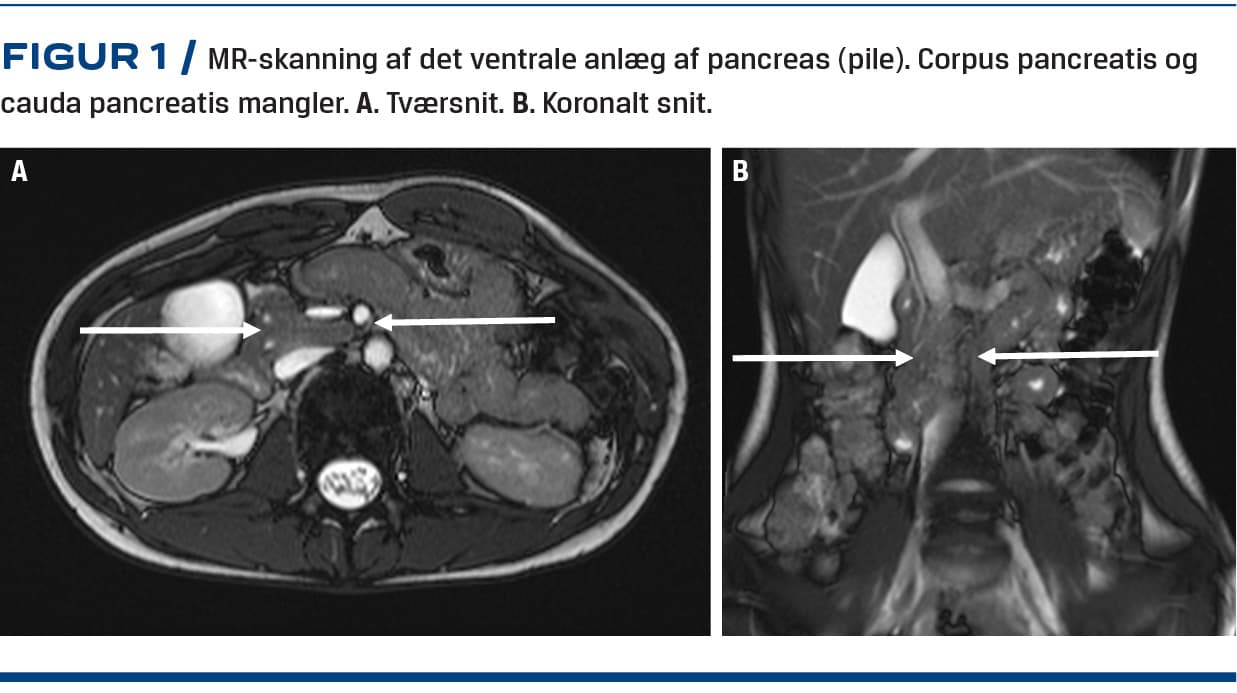

En 18-årig kvinde, som havde fået diagnosticeret Aspergers syndrom, fik over en måned mavesmerter, kvalme, opkastninger, nedsat fødeindtag og vægttab. Hun blev via egen læge henvist til ultralydskanning af abdomen. Ved skanningen blev der påvist bilaterale nyrecyster og rejst mistanke om atrofi af pancreas, da caput pancreatis – men hverken corpus pancreatis eller cauda pancreatis (Figur 1) – kunne ses. Der blev foretaget en gastroskopi og taget biopsier fra duodenum, hvor der blev fundet upåfaldende forhold. Ved en MR-skanning af pancreas påvistes agenesi af det dorsale pancreasanlæg. Størstedelen af symptomerne aftog spontant. På mistanke om pancreassygdom blev patienten henvist til videre ambulant udredning på et universitetshospital. Fraset Aspergers syndrom var patienten tidligere sund og rask. Hun klagede fortsat over mavesmerter, som var lokaliseret under venstre ribbenskurvatur og forværredes postprandialt. Vægttabet var aftaget, og hun havde taget på igen. Der forelå blodprøver, som viste, at hun havde et lavt D-vitamin-niveau (20 nmol/l) og et normalt niveau af glykeret hæmoglobin (41 mmol/mol). En supplerende udredning viste normal faeceselastase (210 µg/g), hvorfor man ikke havde mistanke om pancreasinsufficiens. Derimod blev der påvist hypomagnesiæmi med et magnesiumniveau på 0,64 mmol/l. Pga. hypomagnesiæmien blev patienten undersøgt genetisk for Gitelmans og Bartters syndrom. Disse undersøgelser viste normale forhold. En døgnurinopsamling viste, at der var et renalt betinget magnesiumtab. Der blev foretaget behandling med infusion af magnesium, uden at P-magnesiumniveauet steg nævneværdigt. Der blev påbegyndt behandling med spironolacton mhp. at forebygge dette renale tab.